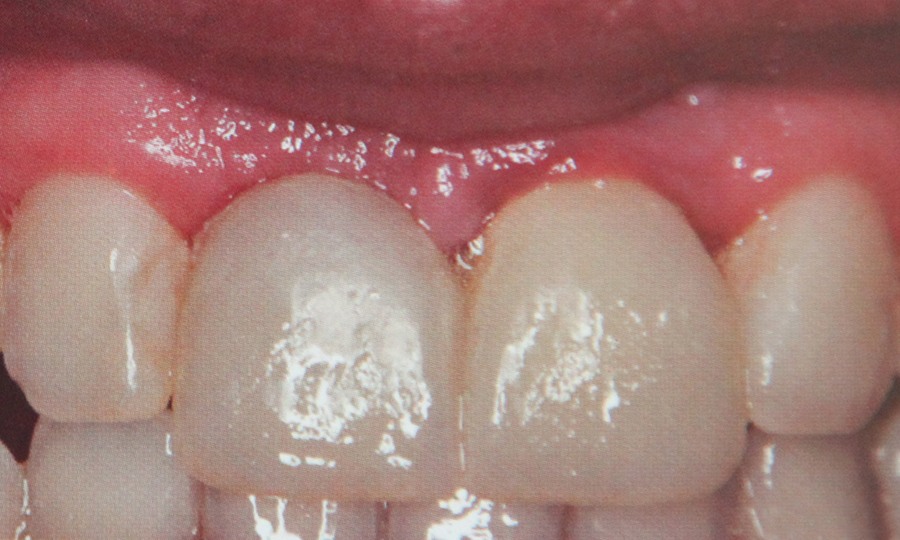

Tehnicile adezive directe de lucru cu materiale bazate pe rasini composite reprezinta o modalitate excelenta de restaurare estetica si minim invaziva a dintilor frontali. Obtinerea rezultatelor estetice asteptate este legata indesolubil de alegerea si utilizarea corecta, conform indicatiilor, a materialelor si tehnicilor de lucru adecvate, fiecarei situatii clinice.

Pentu ca folosim materiale de cea mai buna calitate pentru ca avem o colaborare stransa cu tehnicienii dentari si pentru ca acordam o atentie deosebita dorintelor pacientilor obtinem lucrari protetice care exceleaza prin estetica si functionalitate. Protetica inseamna refacere dentara prin lucrari protetice diverse.

Aceste lucrari pot fi:  - lucrari metalo- ceramice

- ceramica pe zirconiu

- ceramica integrala